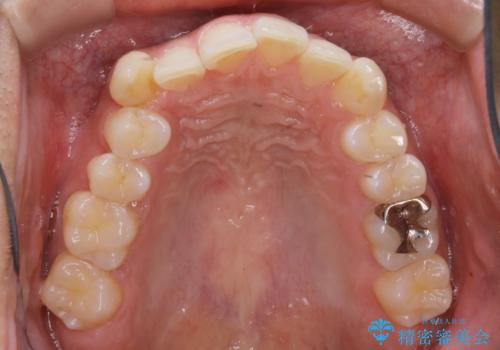

インビザラインで八重歯の治療

- 矯正治療を目的にご来院されました。検査を受けていただき、インビザラインでの矯正治療を行うこととなりました。

八重歯と噛み合わせえお治す必要がありましたが、抜歯を必要とするほどの状態ではなかったため非抜歯プランで治療を開始しました。